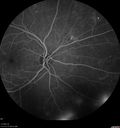

PDR and Vitreous Hemorrhage - High Risk Left Eye - Low Risk Right Eye369 views50 year old man with type I diabetes mellitus for 26 years. New Vitreous Hemorrhage in the left eye. Both eyes have NVE. Both also have foveal hypoplasiaMar 07, 2020